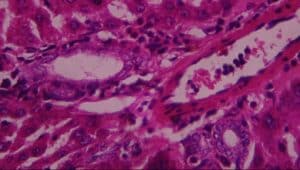

Figure 12: Rat given lead acetate only showing: A-vascular ulceration, B-periportal infiltrates of inflammation, C-vascular congestion and D-necrosis (H&E x 400)

In group III (lead only), the histological evaluation (Figure 6) demonstrated vascular ulceration, vascular congestion, intense necrosis of major liver architecture, and periportal inflammation, further confirming the toxicological effect of lead on the liver. The above histological finding corroborated earlier work done by[26,27,28,29] on vascular congestion of the liver architecture[30] on necrosis of the liver architecture and on the vascular ulceration and periportal inflammation.[31]